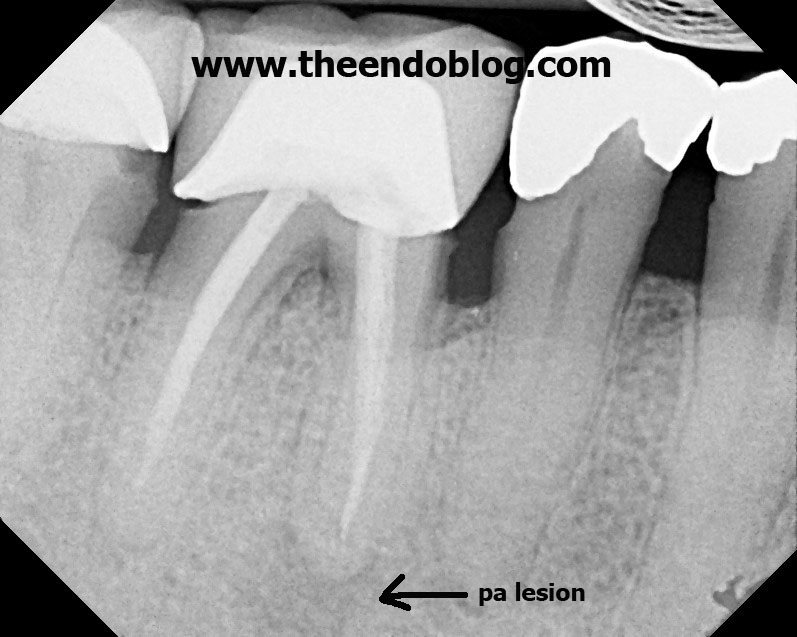

From www.theendoblog.com